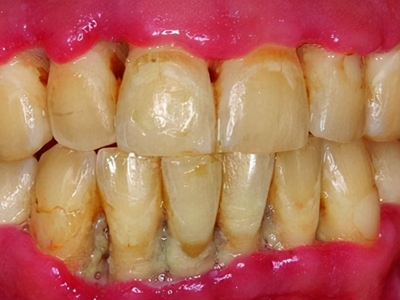

牙龈退缩牙根暴露出现黑斑图

牙龈退缩患者的上排多颗牙齿处的牙龈出现回缩,从而导致牙根外露,外露的牙根上存在黑色的牙菌斑、牙结石,伴有口臭、牙根面敏感等症状。